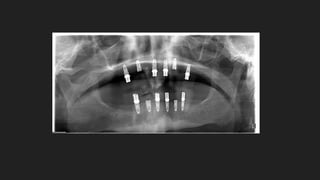

 Antes que nada es necesario disponer de una radiografía Panorámica

 La condición mas importante, es tener suficiente hueso tanto en altura como en anchura, para

que quepa un implante de unos 4 mm de ancho y 12 mm. de largo.

¿Cuáles son losrequisitos necesarios para que sea posible colocar implantes?  Antes que nada es necesario disponer de una radiografía Panorámica  La condición mas importante, es tener suficiente hueso tanto en altura como en anchura, para que quepa un implante de unos 4 mm de ancho y 12 mm. de largo.  El dentista analiza la situación médica del paciente con su historia clínica y las condiciones locales de sus maxilares .  Con todo ello se puede saber cuántos implantes son necesarios, cuántos se pueden colocar y dónde.  También se evalúa la calidad del hueso, y las condiciones de fuerzas que va a recibir la Prótesis sobre los implantes.

Maxilar Superior: 8 implantesbien distribuidos para soportar bien las fuerzas de la mordida y masticar bien.